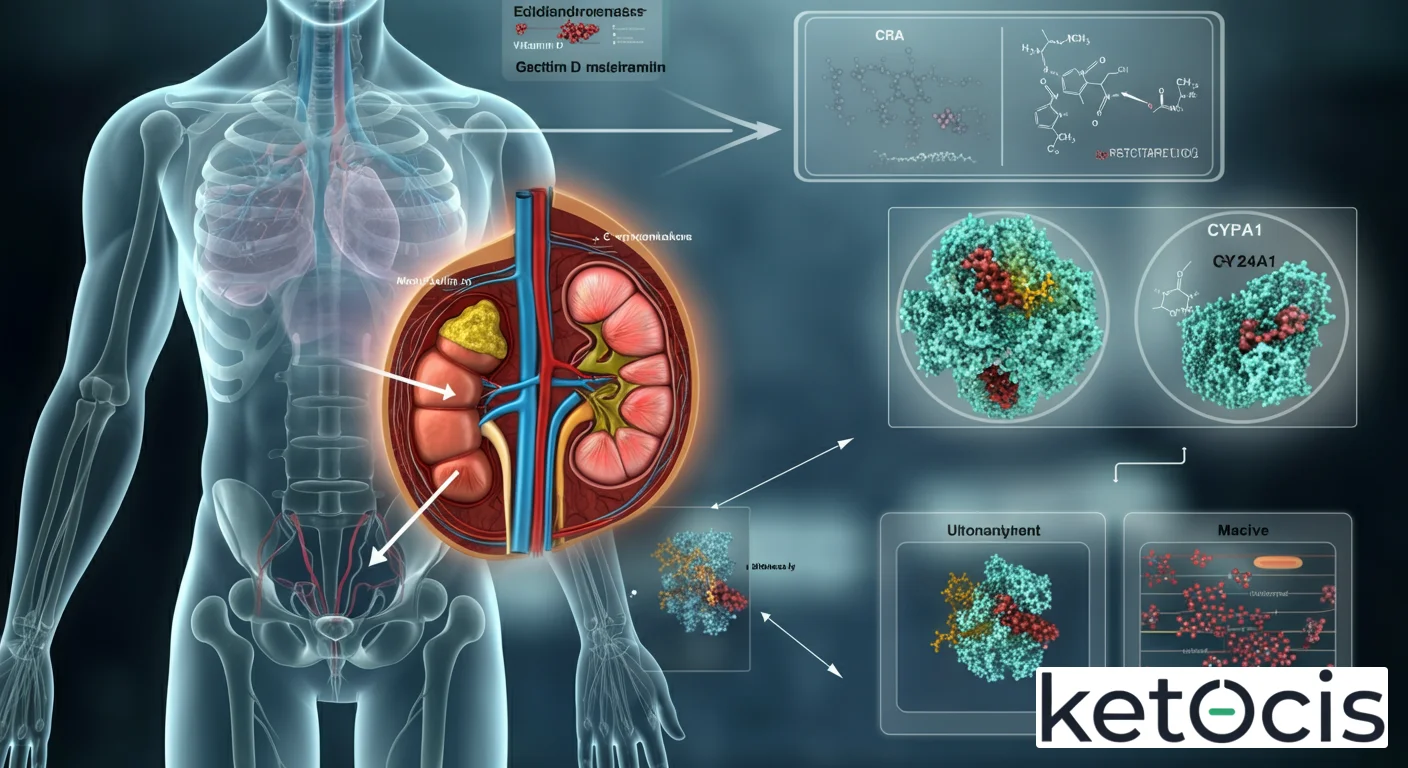

En el intrincado universo de la fisiología humana, donde cada molécula y enzima desempeña un papel coreográfico en el mantenimiento de la homeostasis, la 24-hidroxilasa renal emerge como un director de orquesta silencioso pero fundamental. Conocida científicamente como CYP24A1, esta enzima no solo es crucial para la regulación de la vitamina D, sino que también es un pilar en la prevención de desequilibrios metabólicos que podrían tener consecuencias devastadoras para la salud ósea y sistémica. En esta guía enciclopédica, desentrañaremos su origen, mecanismo de acción, su intrincada regulación y su relevancia en contextos como la cetosis y el ayuno, ofreciendo una perspectiva integral para el lector de «Glosario Ketocis».

La 24-hidroxilasa es una enzima de la familia del citocromo P450, codificada por el gen CYP24A1 en humanos. Aunque su nombre sugiere una ubicación exclusiva en el riñón, esta enzima se expresa en una amplia variedad de tejidos, incluyendo el intestino, la placenta, los osteoblastos, los queratinocitos y las células inmunitarias, además de su preponderancia en los túbulos renales. Sin embargo, su actividad en el riñón es particularmente significativa debido a su papel directo en la inactivación del calcitriol, la forma más potente de la vitamina D.

Mecanismo de Acción: Desactivando la Potencia Hormonal

El mecanismo de acción de la 24-hidroxilasa es ingenioso y vital. Su función principal es catabolizar la vitamina D activa y sus precursores, transformándolos en metabolitos inactivos. Específicamente, la CYP24A1 cataliza dos reacciones principales:

- Hidroxilación del calcitriol (1,25(OH)2D): Convierte el 1,25-dihidroxivitamina D3 en 1,24,25-trihidroxivitamina D3. Este metabolito es posteriormente oxidado a ácido calcitroico, una forma excretable e inactiva.

- Hidroxilación del 25(OH)D: También puede hidroxilar el 25-hidroxivitamina D3, el principal metabolito circulante de la vitamina D, en 24,25-dihidroxivitamina D3 (24,25(OH)2D). Aunque el 24,25(OH)2D tiene cierta actividad biológica, es significativamente menor que la del calcitriol y se considera un paso intermedio en la vía de inactivación.

Estas reacciones actúan como un interruptor de apagado para la vitamina D, garantizando que el cuerpo no acumule cantidades excesivas de calcitriol. Sin esta enzima, incluso dosis moderadas de vitamina D podrían llevar a una toxicidad, caracterizada principalmente por hipercalcemia (niveles elevados de calcio en sangre) y sus consecuencias asociadas, como la calcificación de tejidos blandos y daño renal.